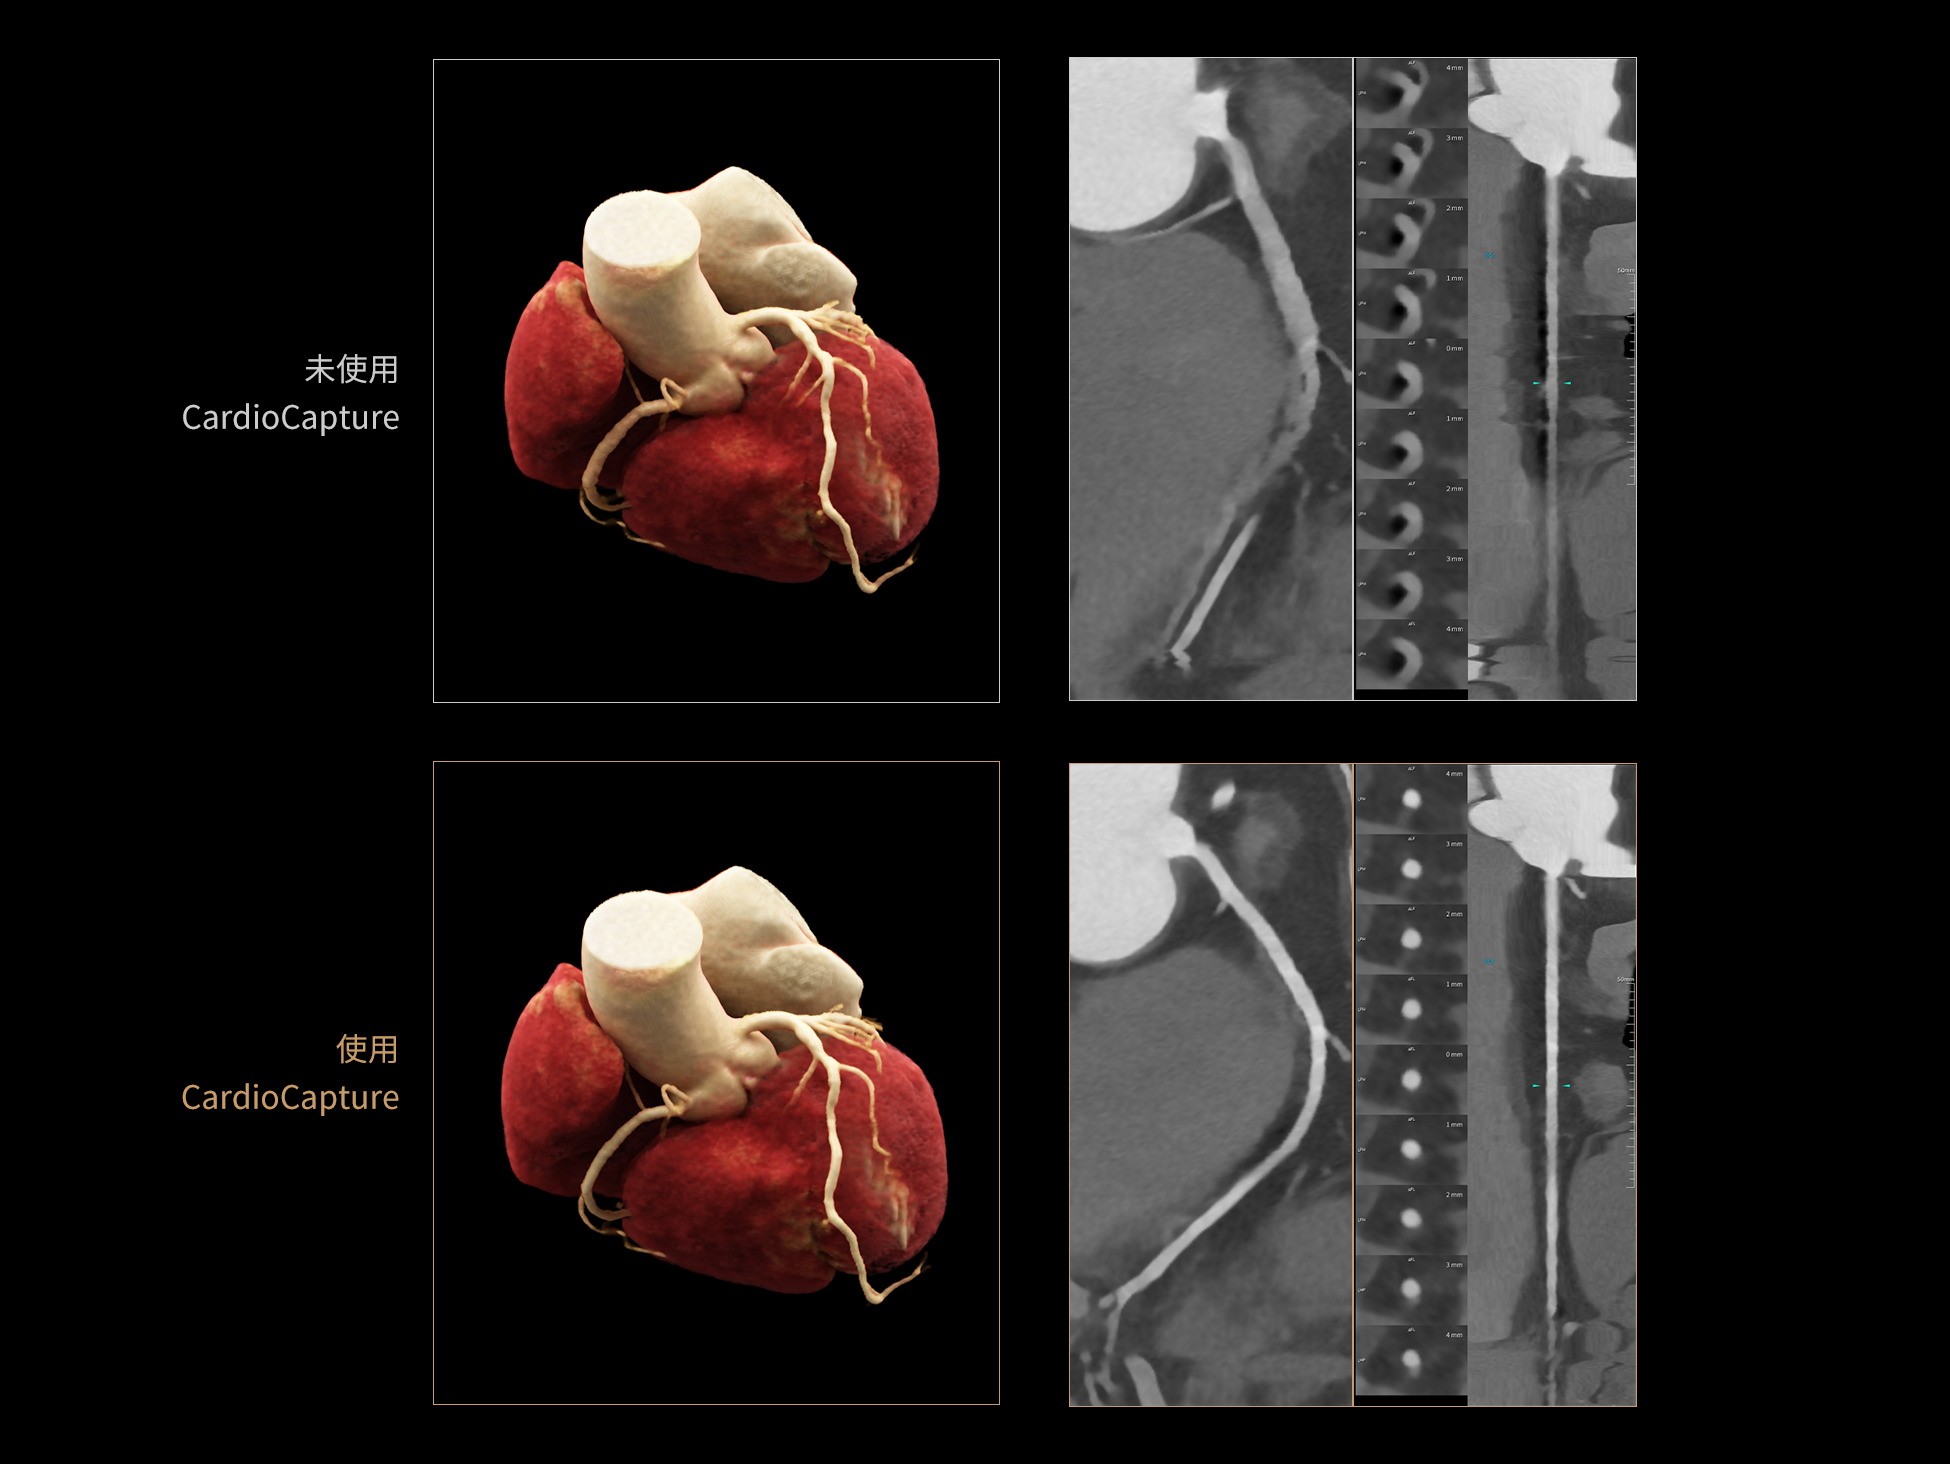

CardioBoost:专属网络设计,重塑心脏影像表现

相同辐射剂量下

低对比度分辨率提升

相同辐射剂量下

空间分辨率提升

相同低对比度分辨率下

辐射剂量减少

相同辐射剂量条件下

图像噪声减少